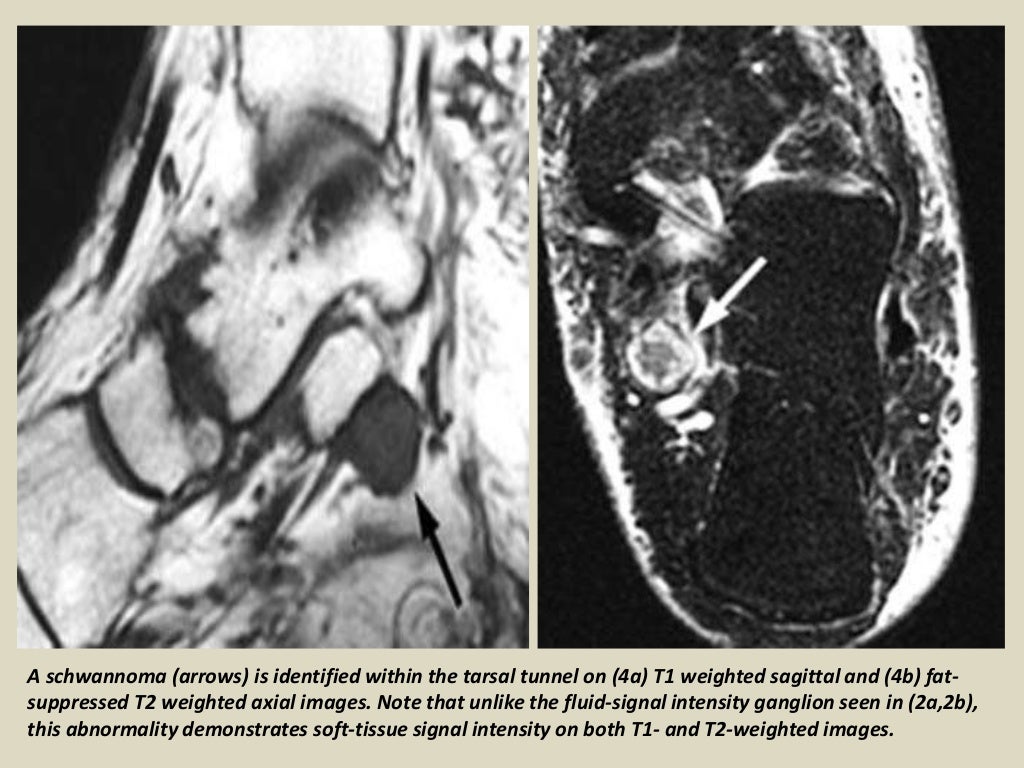

Tarsal Tunnel Syndrome Radiology Key Tarsal Tunnel Syndrome X Ray Mr imaging can accurately depict the contents of the tarsal tunnel and the courses of the terminal branches of the posterior tibial nerve. Tarsal tunnel syndrome refers to an entrapment neuropathy (tunnel syndrome) of the (posterior) tibial nerve or of its branches within. Tarsal tunnel syndrome (tts) is a common entrapment syndrome whose diagnosis can be difficult. This condition is. Tarsal Tunnel Syndrome X Ray.

Tarsal Tunnel Syndrome Radiology Key Tarsal Tunnel Syndrome X Ray This condition is analogous to carpal tunnel. Tarsal tunnel syndrome is a compressive neuropathy of the tibial nerve at the level of the tarsal tunnel which can lead to pain. Tarsal tunnel syndrome refers to an entrapment neuropathy (tunnel syndrome) of the (posterior) tibial nerve or of its branches within. Tarsal tunnel syndrome (tts) is a common entrapment syndrome whose. Tarsal Tunnel Syndrome X Ray.